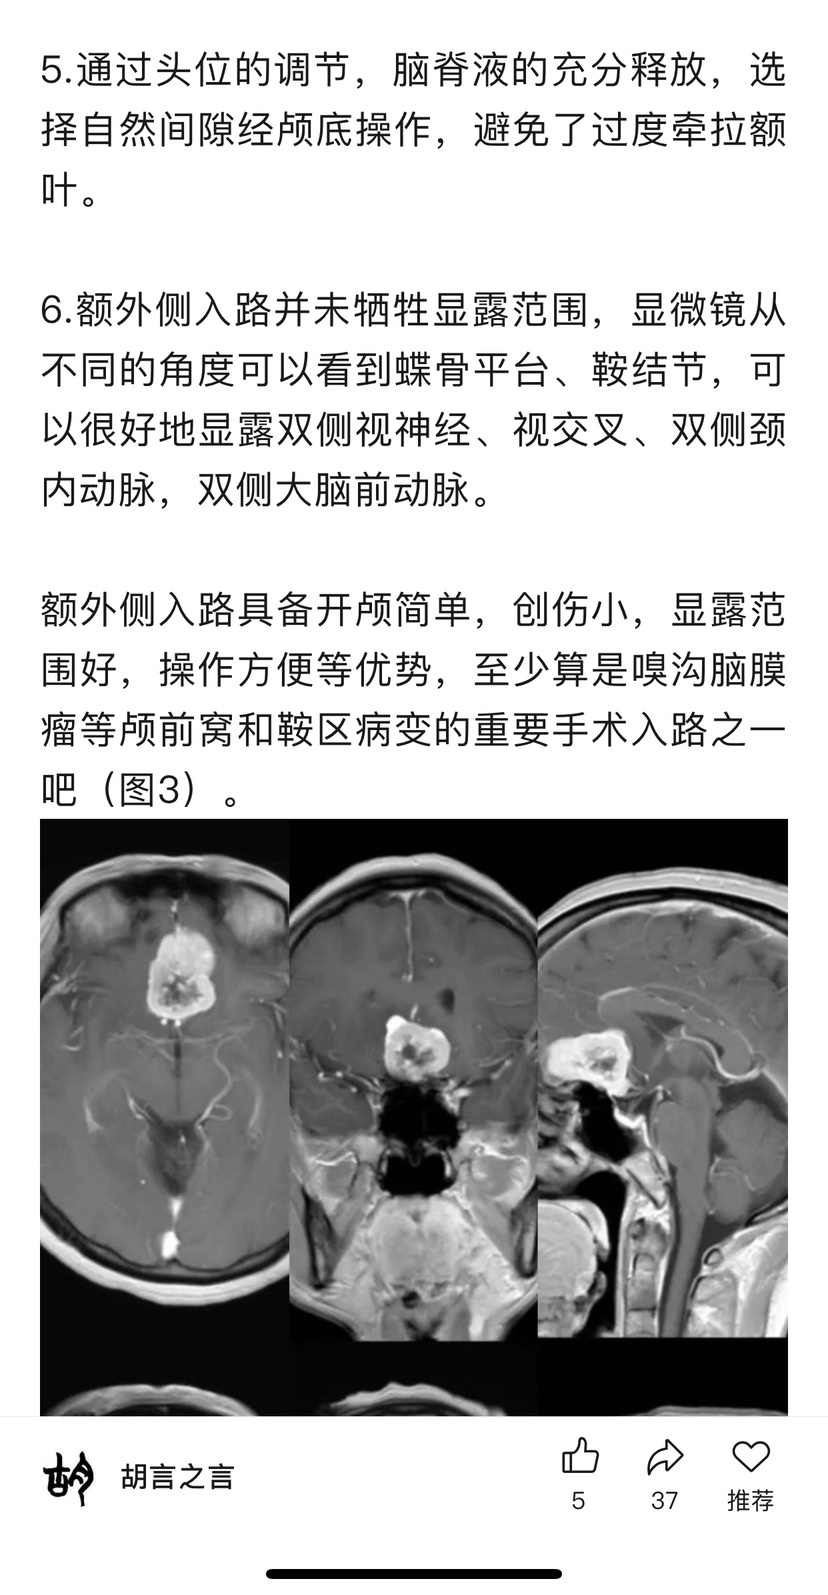

开颅术前参考文献阅读

为方便大家查找原文,特备注公众号信息:2022年03月05日 注册“胡言神外”2025年02月27日 “胡言神外”改名“胡言之言”。(声明:截图分享纯为方便交流,如有侵权或对作者有不良影响,请联系进行相关内容删除,谢谢!)